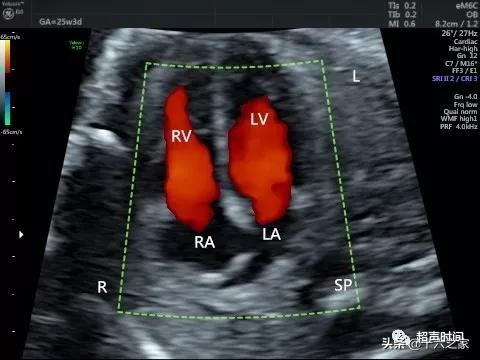

图 5 胎儿四腔心切面未见明显异常